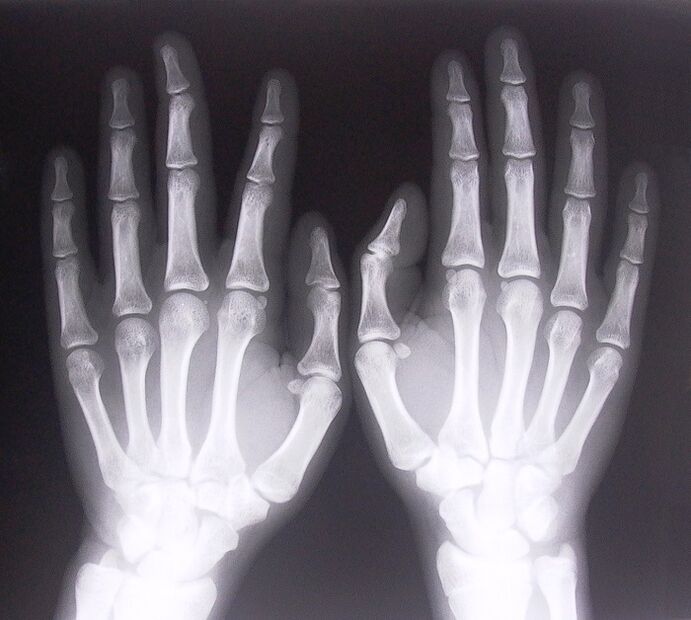

• Stenosing ligamentitis.To find out the cause of the disease, it is necessary to carry out an X-ray examination.Symptoms are typical: painful hand movements, clenched palms.In addition, during extension, a clicking sound is usually heard.

1. Take x-rays.

X-ray as a way to diagnose pain in the joints of the fingers